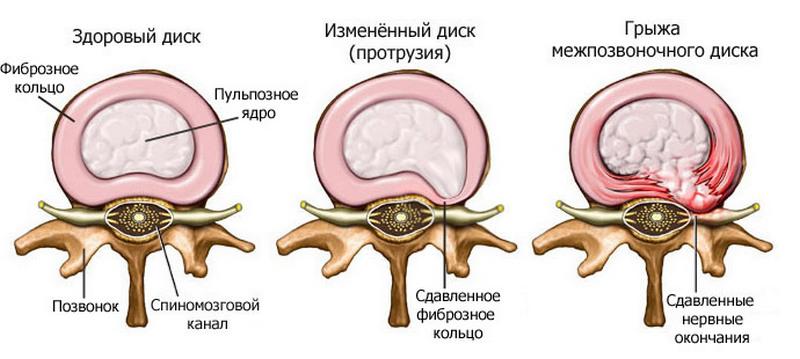

— Наш позвоночник состоит из позвонков, между которыми находятся межпозвонковые диски. Диск состоит из двух основных частей: пульпозного ядра внутри и фиброзного кольца снаружи. Когда идет нагрузка на позвоночник, тело позвонка давит на диск между другим телом позвонка. При этом пульпозное ядро, которое в норме по консистенции напоминает плотный холодец, работает как амортизатор: сплющивается и раздает давление на фиброзное кольцо. Никто не знает почему, но со временем пульпозное ядро начинает терять жидкость и становится сухим.

— Оно уменьшается по объему и перестает выполнять роль амортизатора. Нагрузка начинает падать на фиброзное кольцо, которое сзади наиболее тонкое. В этом месте оно быстрее трескается, и в эти трещины начинает выдавливаться пульпозное ядро. Если оно выпячивается немного, до 6 миллиметров, мы говорим о протрузии (выпячивании). Если происходит выпадение грыжи диска — это пролапс.